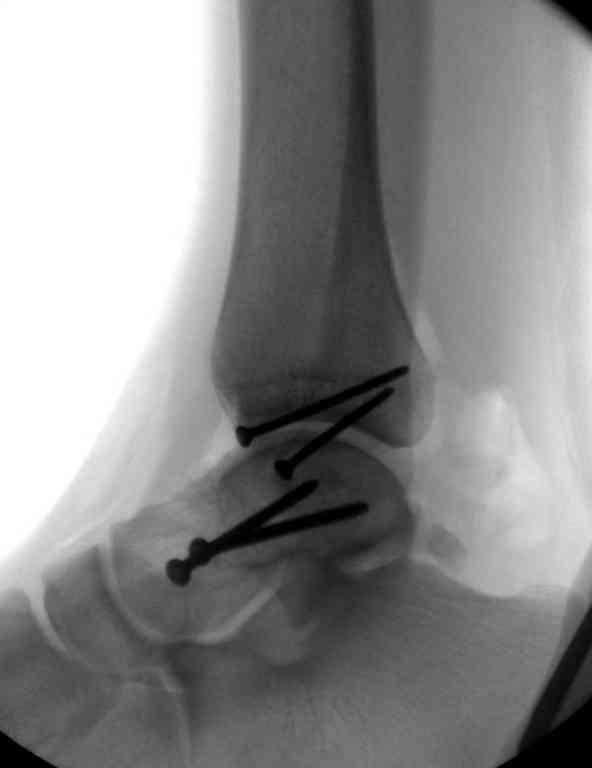

Здесь на фото примеры:

Переломовывих тарана с повреждением медиальной стороны. Через 4 часа после поступления проведена репозиция и фиксация тарана после Irrigation&Debridment. Частичное несращение медиальной лодыжки не беспокоит, вернулся к активному образу жизни. Полная нагрузка разрешена через 11 недель. Финальные снимки через 11 месяцев.